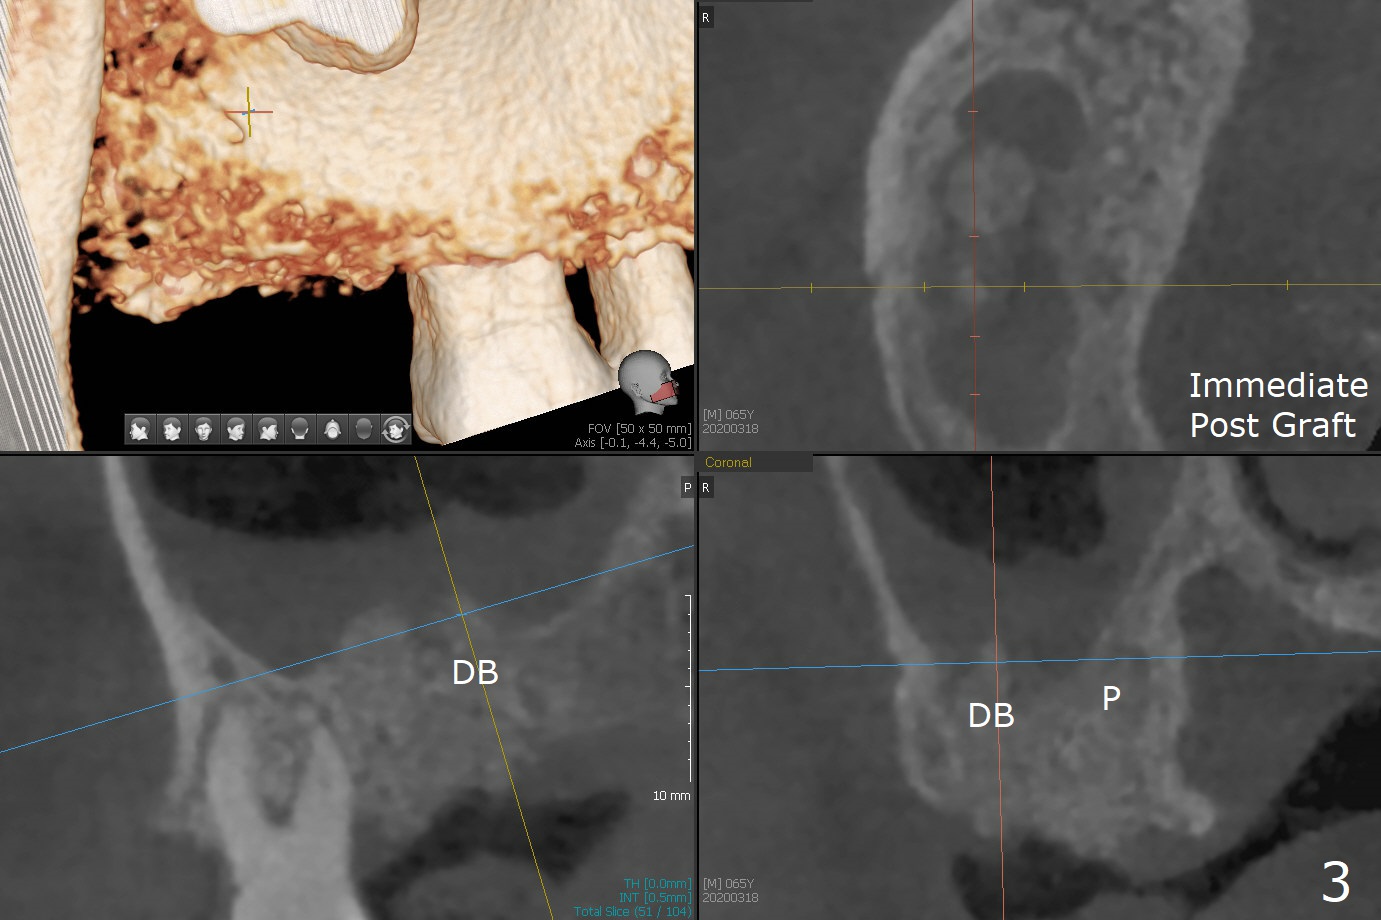

The apices of the mesio-buccal (MB) and disto-buccal (DB) roots are soft when the tooth #2 is extracted. After socket debridement, there is no air leak. Minera-lized cortical and cancellous mix (50/50) hydrated with ~ .25 ml of .3 mg/ml of rhPDGF-BB is placed in MB and DB sockets and pushed upward with a curette. Finally the whole socket is filled up to the crest and a piece of 8x8 mm BioXclude is placed and sutured in placed with 4-0 PGA (Fig.1-3). In fact sinus lift is accomplished moderately MB and DB (Fig.2,3). In fact the density of the bone graft 6 months postop remains the same as immediate postop, similar to the native bone as well (Fig.4,5). With socket preservation, a longer implant will be placed at #2 (Fig.6, as compared 8.5 mm at #15 without bone graft).